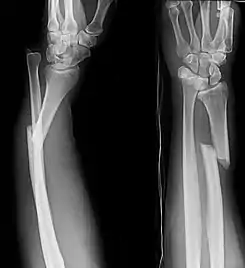

Fractura de Galeazzi

La fractura de Galeazzi consiste en la fractura de la diáfisis radial con luxación del cúbito a nivel de la articulación radiocubital distal. La lesión produce una disrupción a nivel de la articulación de la muñeca

![]() Radiografías anteroposterior y lateral de un antebrazo con la fractura de Galeazzi. | ||